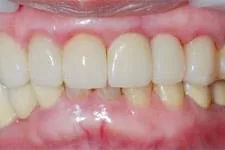

我們在植牙領域的突破,克服患者對手術的恐懼,也同時幫助患者告別了缺牙的痛苦,讓患者重新擁有一口完美的牙齒。

↑ 治療後:微創立即植牙恢復美麗外觀